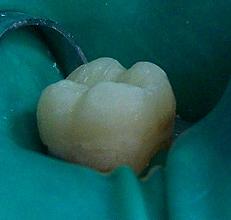

Cuando la corona del diente ha perdido demasiada estructura, es necesario, no sólo obturar la cavidad, si no también proporcionar con la restauración una protección que evite posibles fracturas del diente a medio y largo plazo.

Un diente con endodoncia por los motivos comentados anteriormente tiene un riesgo mayor que un diente vital a sufrir algún tipo de fractura. Esto puede tener en muchos casos consecuencias muy graves para el diente, implicando su extracción.

Por estos motivos en ocasiones es necesario recubrir el diente completamente para protegerlo al máximo. También, si la cantidad de tejido dentario es muy limitada, puede ser necesario el uso de refuerzos radiculares denominados pernos o postes.